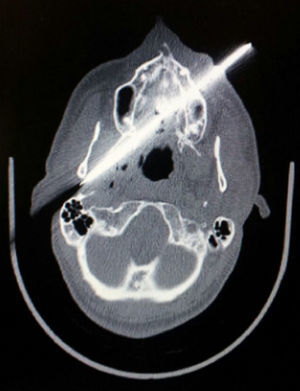

Tras comprobar condiciones de estabilidad hemodinámica se realizó un estudio radiológico (figs. 2 y 3) y se decidió intervención quirúrgica urgente por probable compromiso de la vía aérea basado en la trayectoria del arma.

Imagen de tomografía axial computarizada (TAC) donde se muestra cuerpo extraño (cuchillo) que se introduce por región maxilar izquierda atravesando paladar duro y cavidad oral. Su punta provoca una subluxación de la articulación temporomandibular y lesión parafaríngea derecha con burbujas aéreas.